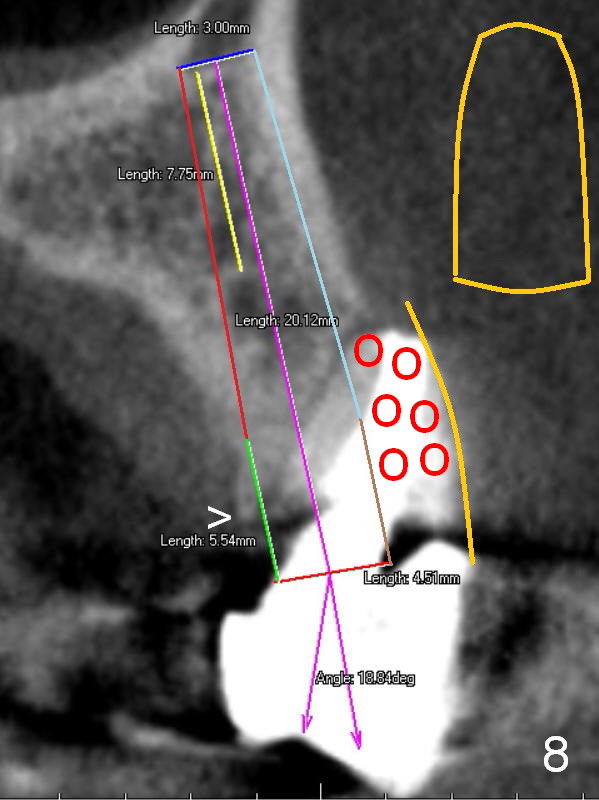

After extraction, the bottom of the socket must be oblique (Fig.9 arrowheads). As usual, osteotomy is initially at the junction of palatal (Fig.10 P) 1/3 and middle 1/3 perpendicular to the plate. Once the drill gets engaged, the trajectory is to be changed (Fig.11 curved arrow) so that the apical end of the osteotomy (red line) is as close to the buccal plate (B) as possible. The purpose is to keep the palatal end of the osteotomy as palatal as possible. In spite of the effort, an angled abutment is expected, as large as 20 degree (Fig.8 purple angle).